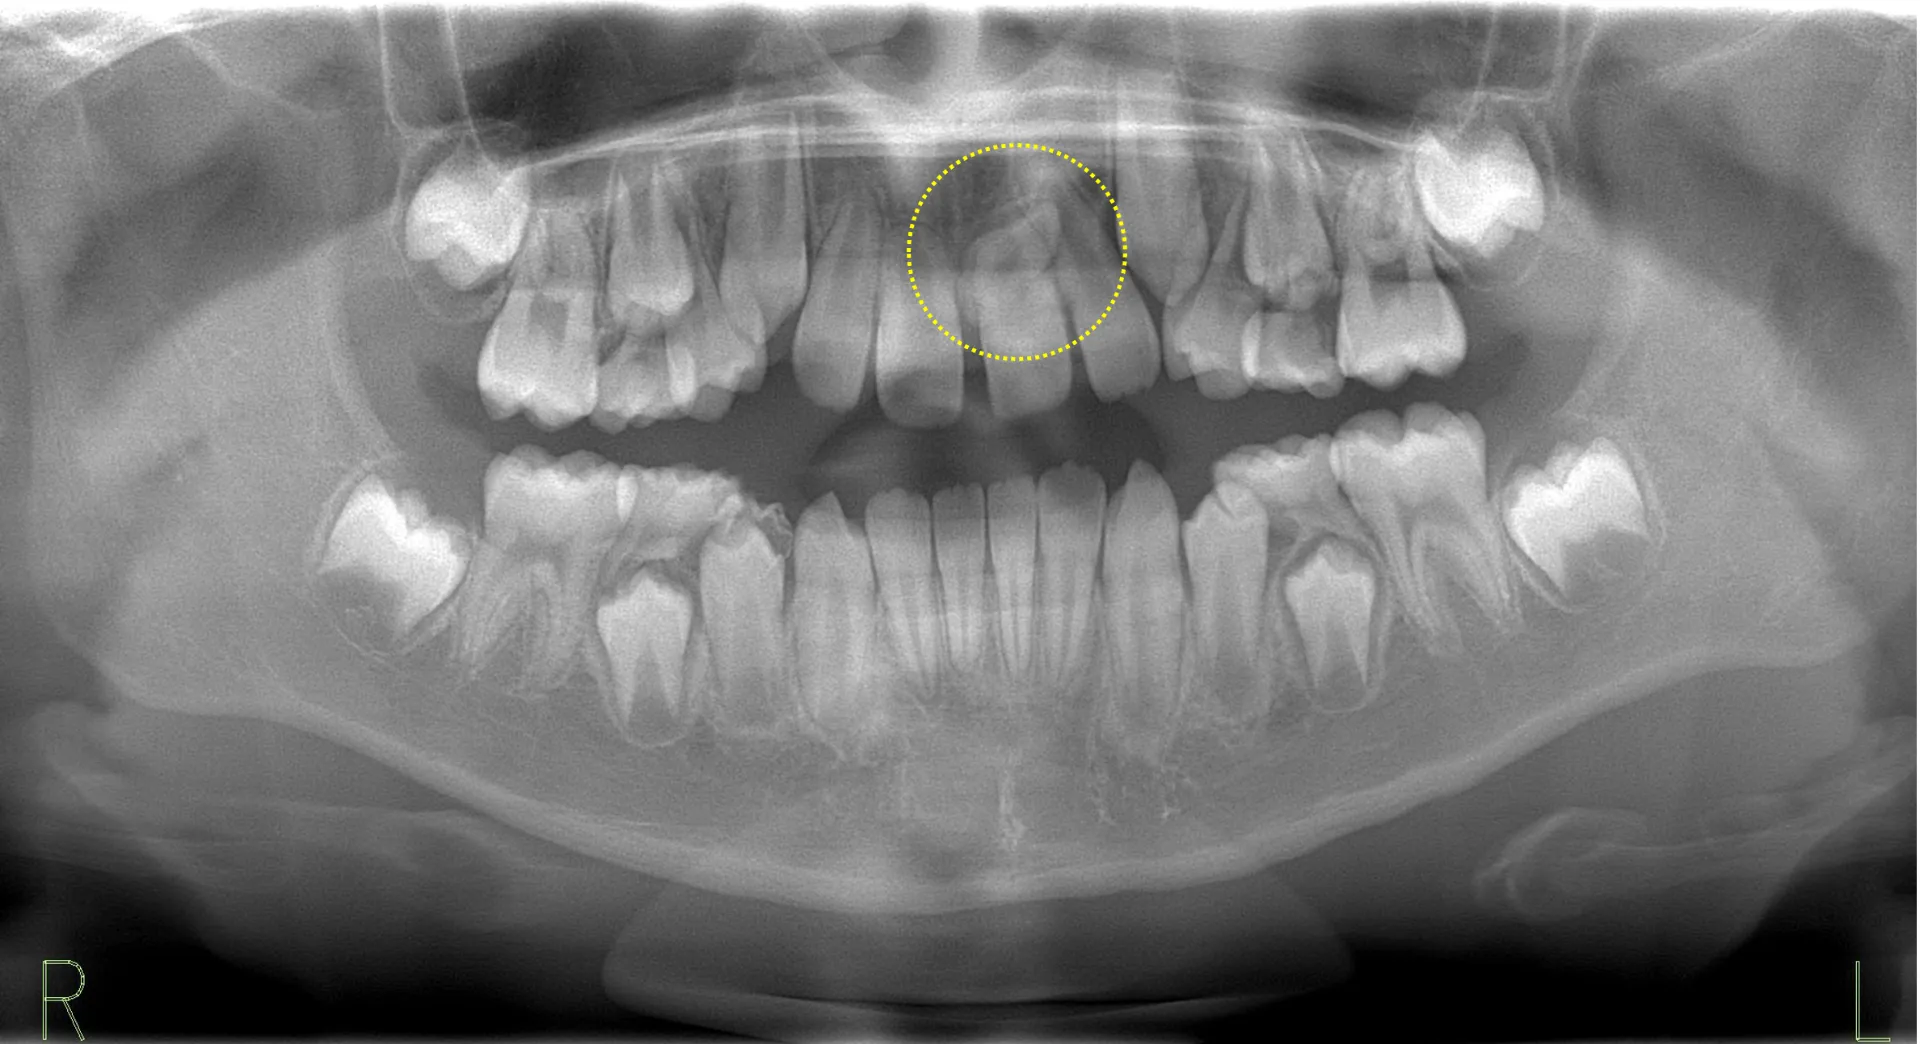

正中埋伏過剰歯